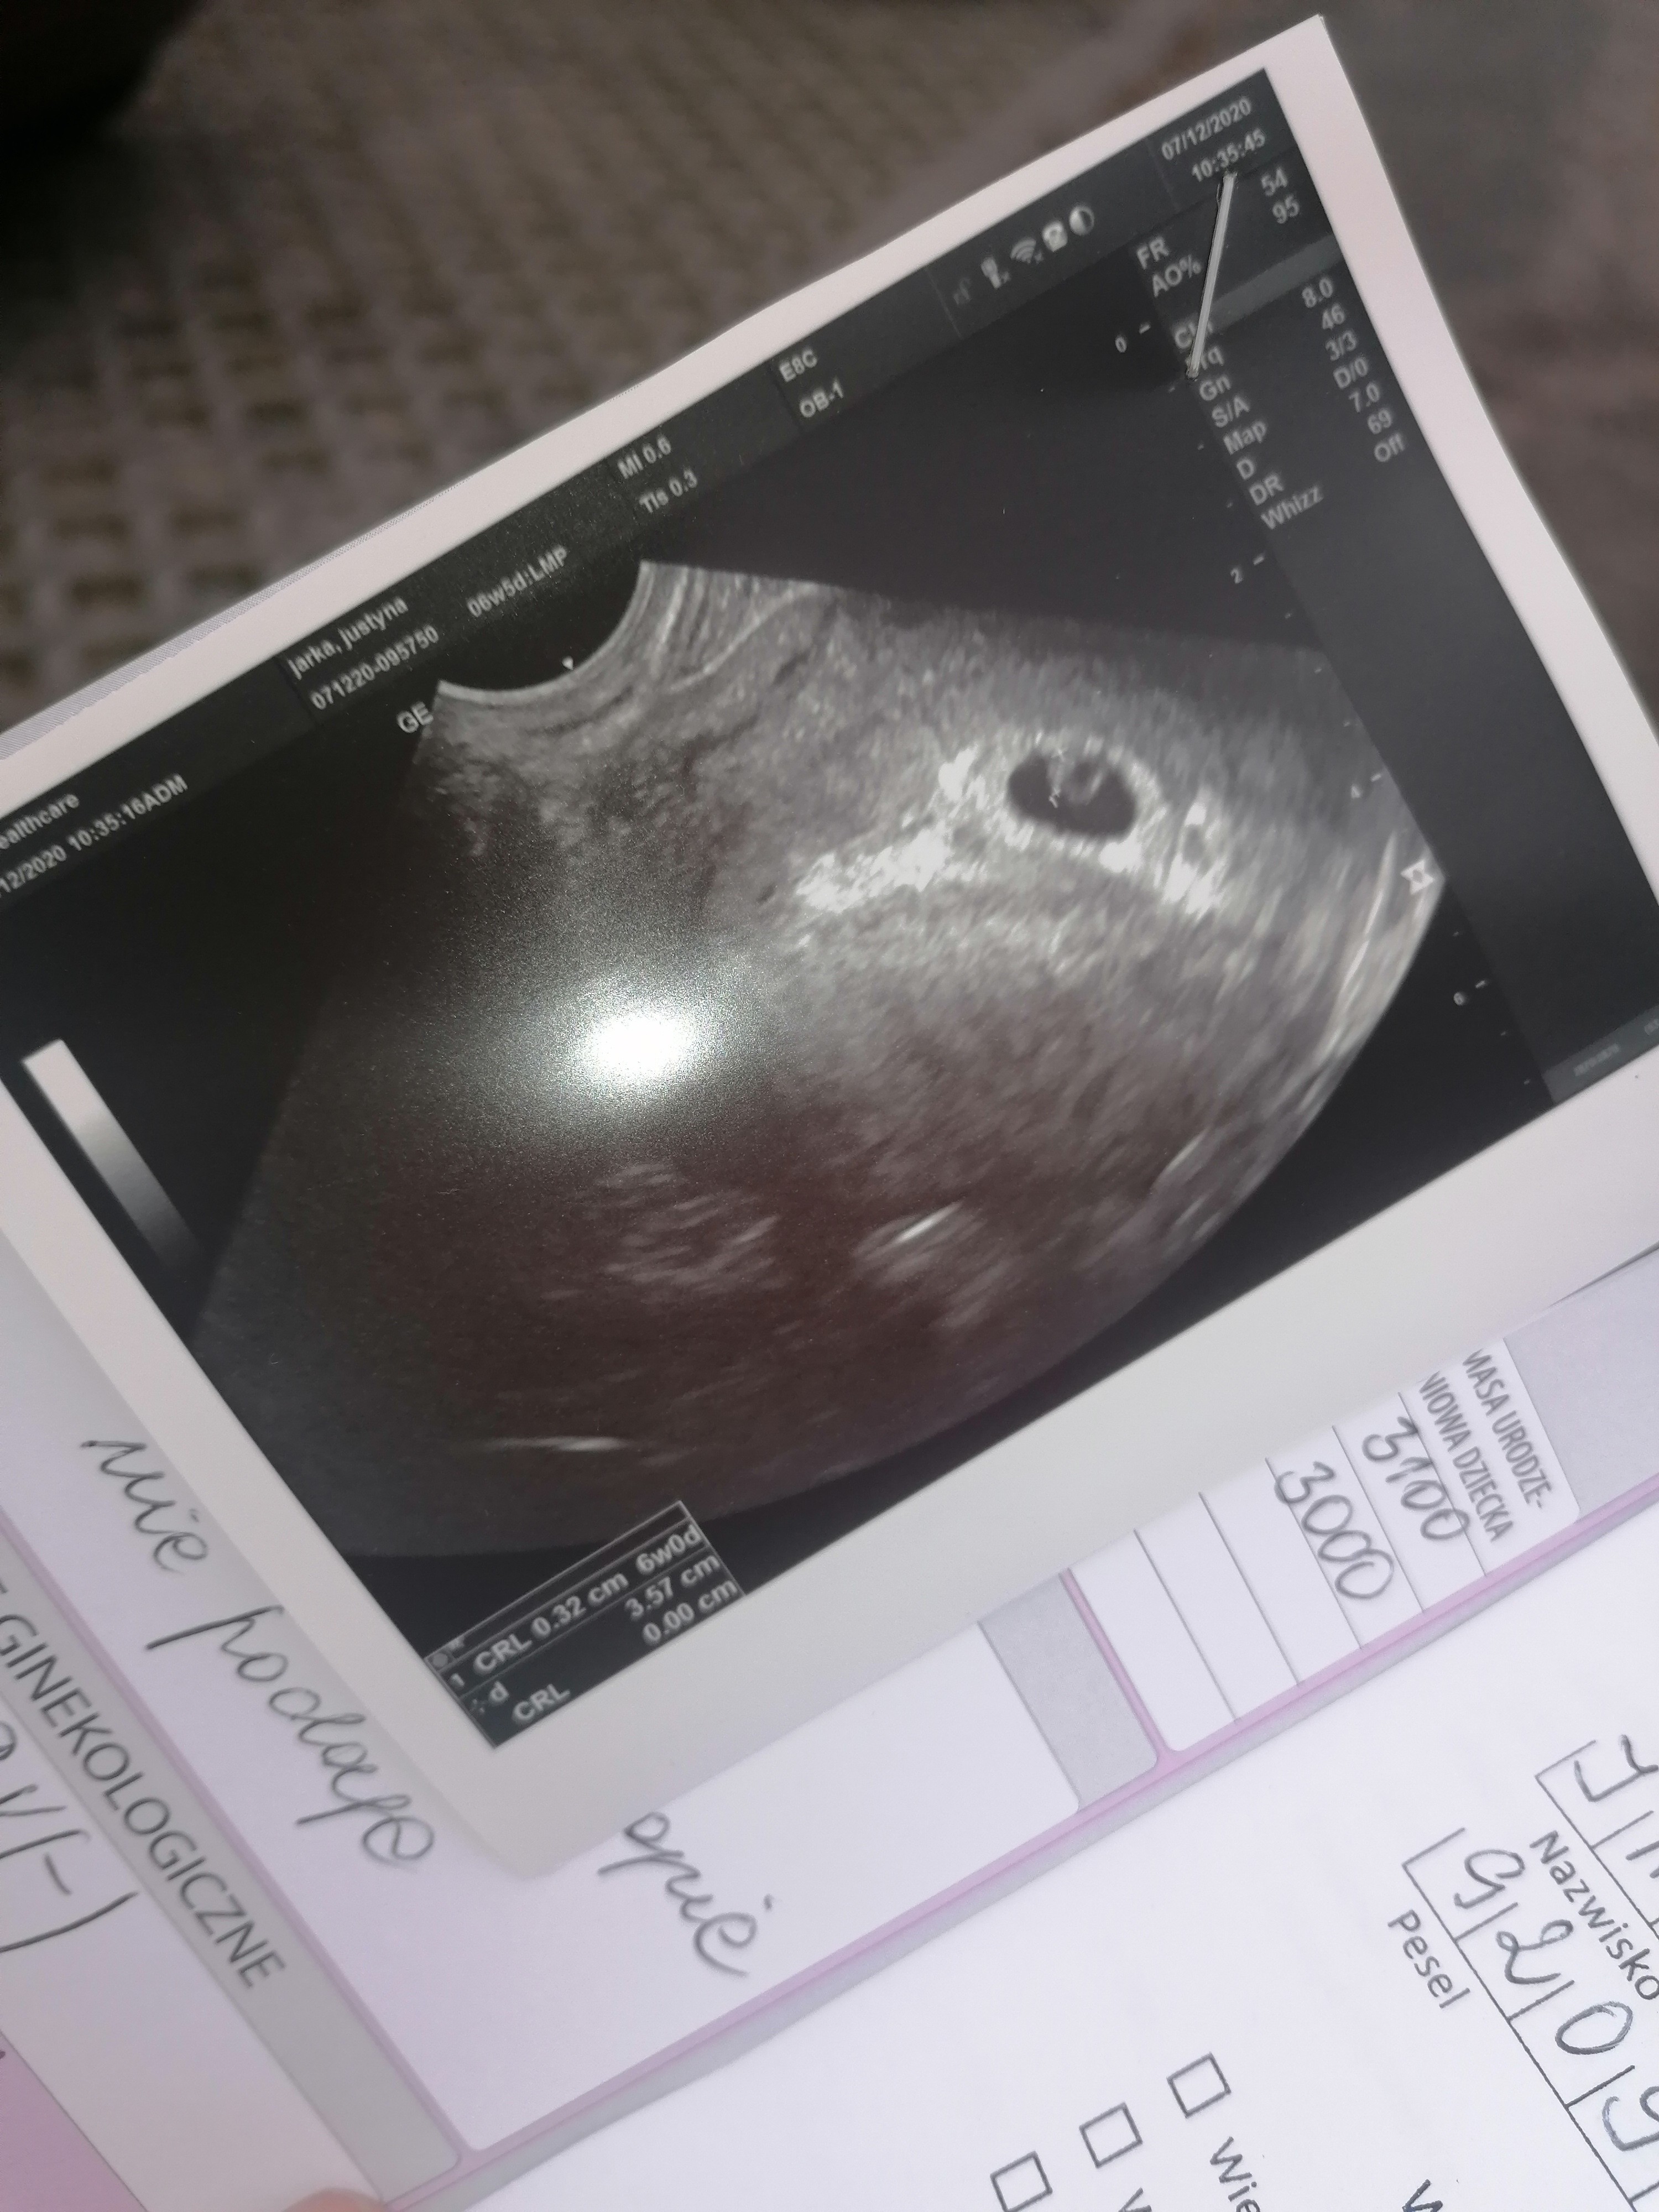

Ciąża żywa 6tc ❤️❤️❤️ Pozdrawiam wszystkie Mamitki z różnymi zdjęciami USG bo każda ciąża jest inna 😘💕

Załączniki

• IMG_20201207_110053.jpg